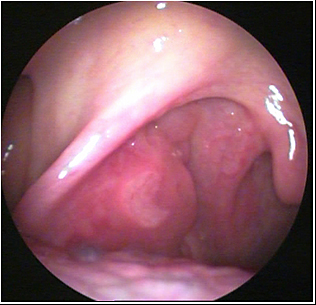

JFC Poliposis nasal

JFC Poliposis nasal simple

JFC Poliposis nasal.

JFC Poliposis nasal bilateral.